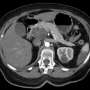

In a shocking turn of events, Irene Blair, who was initially diagnosed with pancreatic cancer less than a year ago, faced a devastating prognosis of only six to eight months to live after her cancer advanced to stage 4. However, the announcement of a promising new drug is changing the narrative for her and many others facing similar battles.

Recent reports from Cancer Research UK confirm that this new therapy targets the aggressive nature of pancreatic cancer, potentially extending life expectancy and improving quality of life for patients. Medical experts emphasize that advancements in treatment options are crucial, especially given that pancreatic cancer has one of the lowest survival rates among cancers.